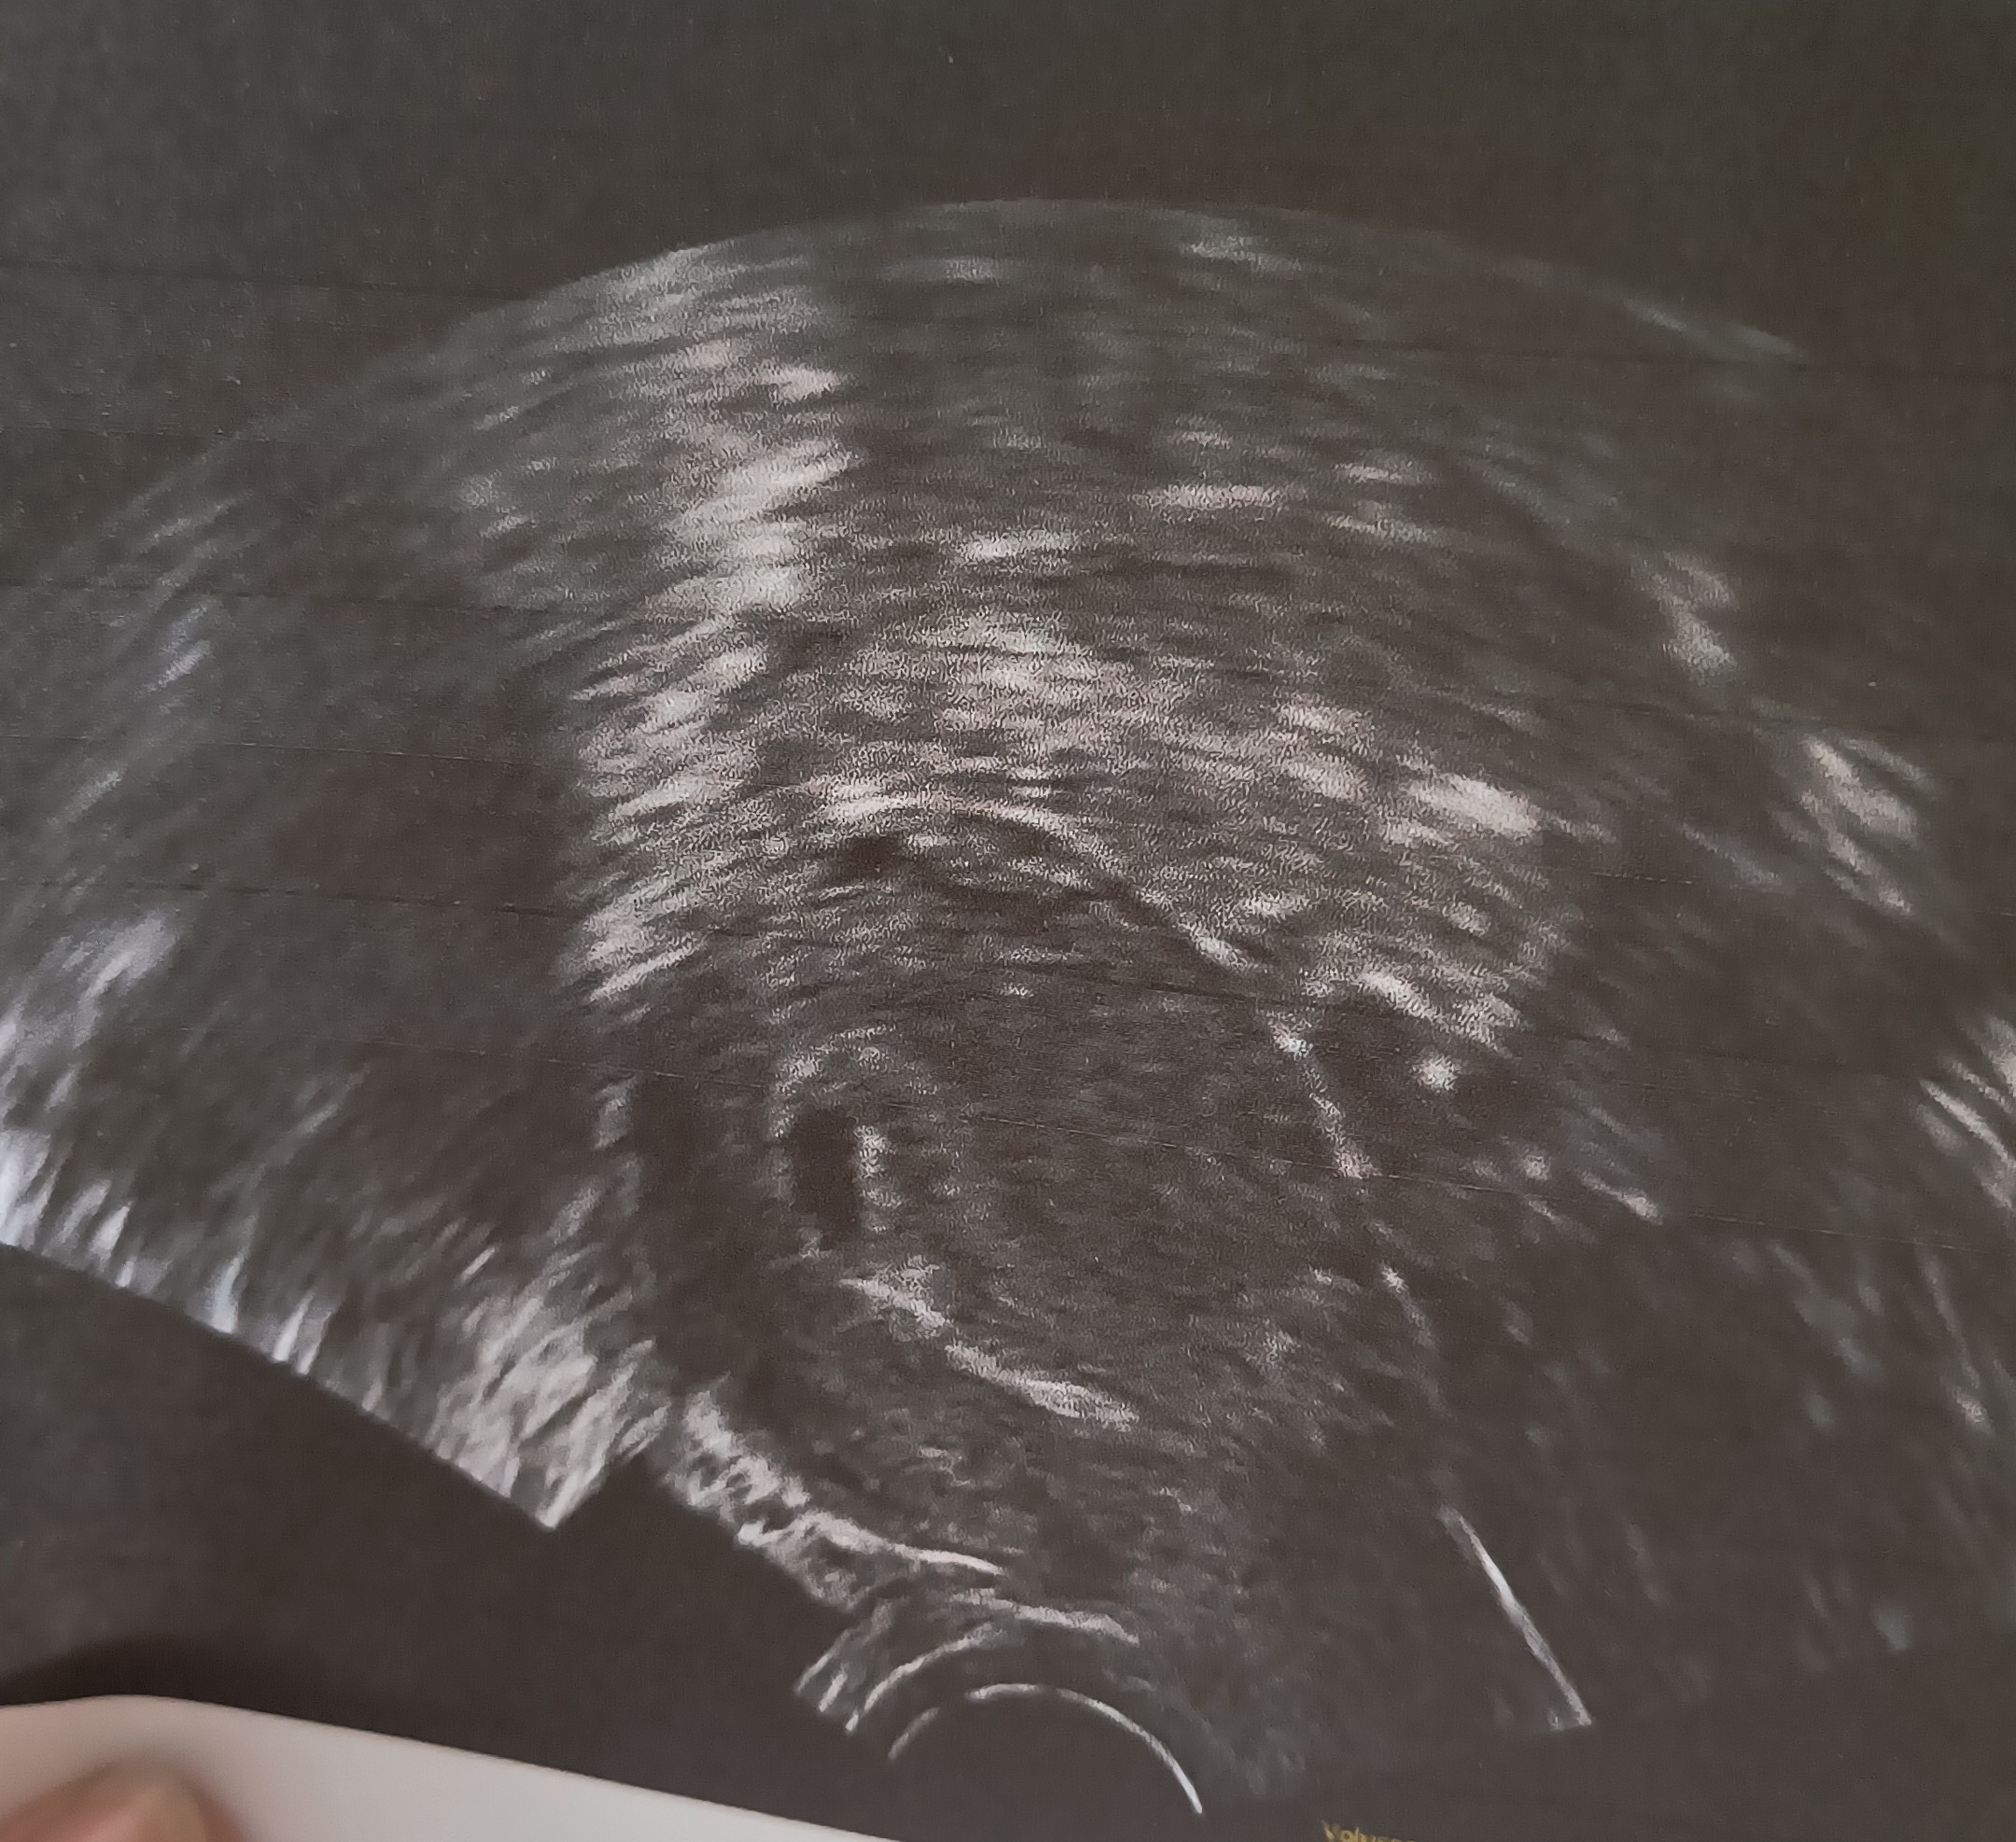

Jednak się udało ponad 4 tydzień ciąży. Kamień spadł mi z serca jak jednak dowiedziałam się że ciąża jest prawidłowo umiejscowiona. Ale jesteśmy na podtrzymaniu i lekarz zalecił luteine 3 razy dziennie i również przepisał mocniejszy kwas foliowy. Dziękuję wam wszystkim za wsparcie. ☺️☺️😚❤️

IMG-20240716-WA0005~2.jpeg

Jednak się udało ponad 4 tydzień ciąży. Kamień spadł mi z serca jak jednak dowiedziałam się że ciąża jest prawidłowo umiejscowiona. Ale jesteśmy na podtrzymaniu i lekarz zalecił luteine 3 razy dziennie i również przepisał mocniejszy kwas foliowy. Dziękuję wam wszystkim za wsparcie. ☺️☺️😚❤️Zobacz załącznik 1648046